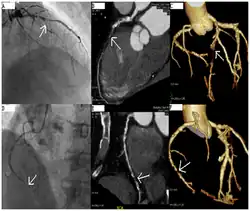

Coronary angiography of a critical sub-occlusion of the common trunk of the left coronary artery and the circumflex artery. (See arrows)

Angiography (left) and CT (middle and right) of chronic total occlusion lesions at the left anterior descending coronary artery (LAD) and right coronary artery (RCA).

CT angiography can act as a less invasive alternative to Catheter angiography. Instead of a catheter being inserted into a vein or artery, CT angiography involves only the injection of a CT-visible dye into the arm or hand via an IV line. CT angiography lowers the risk of arterial perforation and catheter site infection. It provides 3D images that can be studied on computer, and also allows measurement of heart ventricle size. Infarct area and arterial calcium can also be observed (however those require a somewhat higher radiation exposure). That said, one advantage retained by Catheter angiography is the ability of the physician to perform procedure such as balloon angioplasty or insertion of a stent to improve blood flow to the artery.[8]